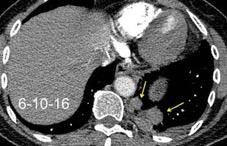

25. DERRAME PLEURAL. TRAUMA

26. DERRAME PLEURAL UNILATERAL. ENF. SUBDIAFRAGMÁTICA

Hemorrágica………….30-70 UH

Extravasación iv. con sangrado activo……….>90 UH

“Simpático”………….,,,,<15 UH

Durso AM et al. Penetrating Thoracic Injury. Radiol Clin N Am 2015.